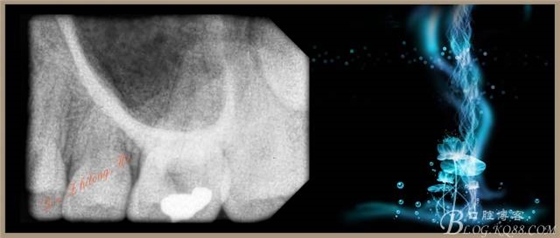

檢查:#26PO可見大面積黑色充填物,腭側(cè)充填物脫落少許,缺損深及髓腔,探(+++),叩(-),冷試驗(yàn)敏感。X-ray示PO充填物近髓腔,根尖周無明顯異常。

4、試主尖,側(cè)壓充填法根充,拍根充片,聚羧酸鋅暫封。